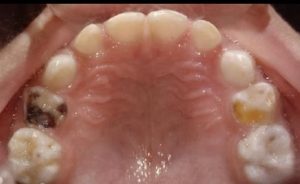

We at the Department of Pediatric & Preventive Dentistry focus on comprehensive oral health care needs of a child from infancy to adulthood and provide comprehensive, therapeutic as well as preventive care to all children including those with special care needs.

Treatment and Services